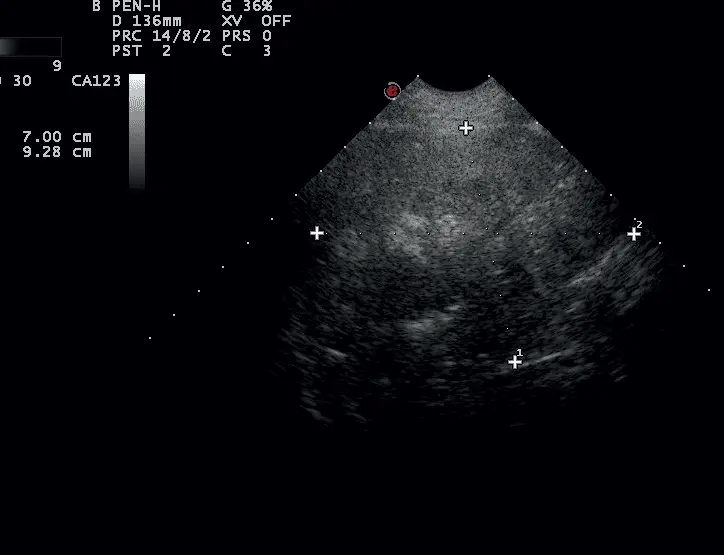

Wykonano ponownie badanie klinicznie, w którym stwierdzono brak trzeszczeń nad polami płucnymi, ogniskowo lewostronnie zaostrzony szmer oskrzelowy w dolnych polach płucnych. Wykonano kontrolne badanie USG płuc, w którym stwierdzono w siódmej przestrzeni międzyżebrowej lewostronnie w linii przymostkowej widoczny opisywany wcześniej obszar konsolidacji, o wyraźnie mniejszym zakresie, częściowo ukryty pod żebrem, bez widocznego bronchogramu powietrznego. Obraz wskazywał na proces gojenia z możliwym częściowym zwątrobieniem płuca (zdj. 3). Antybiotykoterapia została utrzymana, a dodatkowo dodano syrop Pectodrill 2 razy dziennie po 5 ml przez 7 dni.